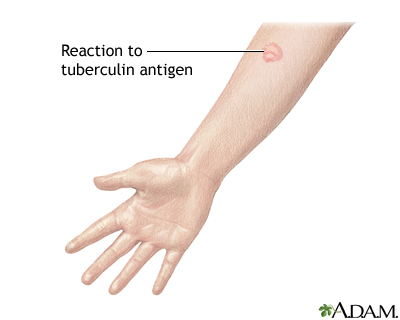

- Tuberculin skin test (also called a PPD test)

TB is preventable, even in those who have been exposed to an infected person. Skin testing for TB is used in high-risk populations or in people who may have been exposed to TB, such as health care workers.

People who have been exposed to TB should have a skin test as soon as possible and have a follow-up test at a later date, if the first test is negative.

A positive skin test means you have come into contact with the TB bacteria. It does not mean that you have active TB or are contagious. Talk to your provider about how to prevent developing active TB.

People who have had BCG may still be skin-tested for TB. Discuss the test results (if positive) with your provider.